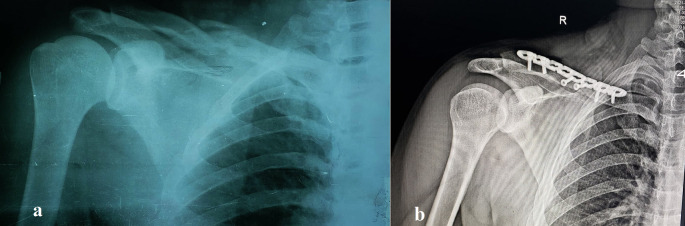

Background: This study assessed the functional outcomes and complications of open reduction and internal fixation (ORIF) using precontoured superior clavicle locking plates for displaced midshaft clavicular fractures.

Methods: In a prospective two-center study at Al-Thawra Modern General Hospital and Kuwait University Hospital, Sana'a, Yemen, from January 2018 to September 2024, 65 patients (≥18 years) with closed, displaced midshaft clavicular fractures (displacement >2 cm, shortening >2 cm, comminution, or skin tenting) underwent ORIF. Functional outcomes were evaluated six months postoperatively using the University of California, Los Angeles (UCLA) shoulder rating score. Data were analyzed using SPSS version 26.

Results: The mean patient age was 32.09 years (83.1% male, n=54). Road traffic accidents were the primary mechanism of injury (66.2%, n=43). At 6 months, the mean UCLA score was 32.46 ± 2.54, with 98.5% (n=64) achieving good or excellent outcomes (UCLA score ≥27) and 1.5% (n=1) fair/poor. Complications included hardware irritation (1.5%, n=1), hardware failure (3.1%, n=2), and superficial infections (1.5%, n=1). All patients (100%) reported satisfaction with their outcomes. The UCLA scores varied significantly according to injury mechanism, side, and age, with older patients showing lower scores.

Conclusion: ORIF with precontoured locked plates yielded promising functional outcomes, high patient satisfaction, and low complication rates. However, the observational design, lack of a control group, and 6-month follow-up limit broader conclusions. Larger controlled studies are needed to validate these findings and guide the optimal management of displaced midshaft clavicular fractures.